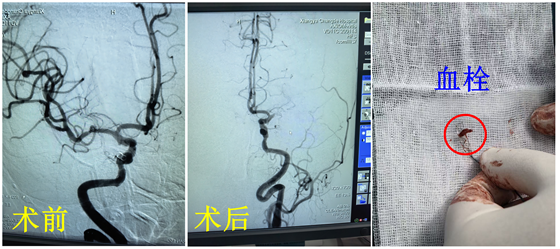

2月11日,一位刚升级当母亲的33岁年轻患者,1月前无明显诱因出现发作性四肢肢体抽搐...